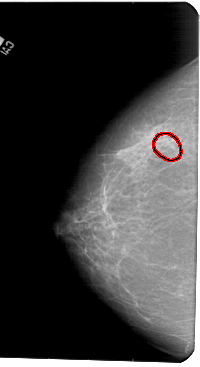

A_1441_1.LEFT_MLO

FILE: A_1441_1.LEFT_MLO.OVERLAY

TOTAL_ABNORMALITIES 1

ABNORMALITY 1

LESION_TYPE CALCIFICATION TYPE PLEOMORPHIC DISTRIBUTION CLUSTERED

ASSESSMENT 4

SUBTLETY 2

PATHOLOGY BENIGN

TOTAL_OUTLINES 1

BOUNDARY